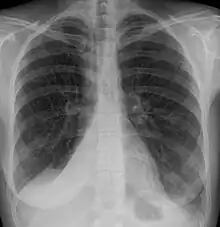

| Atelectasis of a person's right lung | |

Atelectasis is the partial collapse or closure of a lung resulting in reduced or absent gas exchange. It is usually unilateral, affecting part or all of one lung.[2] It is a condition where the alveoli are deflated down to little or no volume, as distinct from pulmonary consolidation, in which they are filled with liquid. It is often referred to informally as a collapsed lung, although more accurately it usually involves only a partial collapse, and that ambiguous term is also informally used for a fully collapsed lung caused by a pneumothorax.[1]

Clinically significant atelectasis is generally visible on chest X-ray; findings can include lung opacification and/or loss of lung volume. Post-surgical atelectasis will be bibasal in pattern. Chest CT or bronchoscopy may be necessary if the cause of atelectasis is not clinically apparent. Direct signs of atelectasis include displacement of interlobar fissures and mobile structures within the thorax, overinflation of the unaffected ipsilateral lobe or contralateral lung, and opacification of the collapsed lobe. In addition to clinically significant findings on chest X-rays, patients may present with indirect signs and symptoms such as elevation of the diaphragm, shifting of the trachea, heart and mediastinum; displacement of the hilus and shifting granulomas.[10]